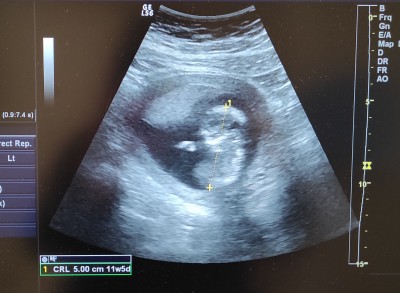

Cinsiyet tahmini yapabilen anlayan var mi

Tahmin yapabilen var mı 15 haftalik teyzeleri

İçime erkek doğdu tatlım

Belli olmuyo ki

Evet belli olmuyor. Dr ikidir cinsiyet kısmını göstermeden fotoğraf çekmeme izin verdi. Ben hani görüntü olarak ne hissediyorsunuz gibisinden sormak istedim

Kese yuvarlaksa kiz diyolar ama. Hic bilgili degilim. Kizda olsa erkekde olsa. Hayirlisiyle olsun. Omru uzun olsun